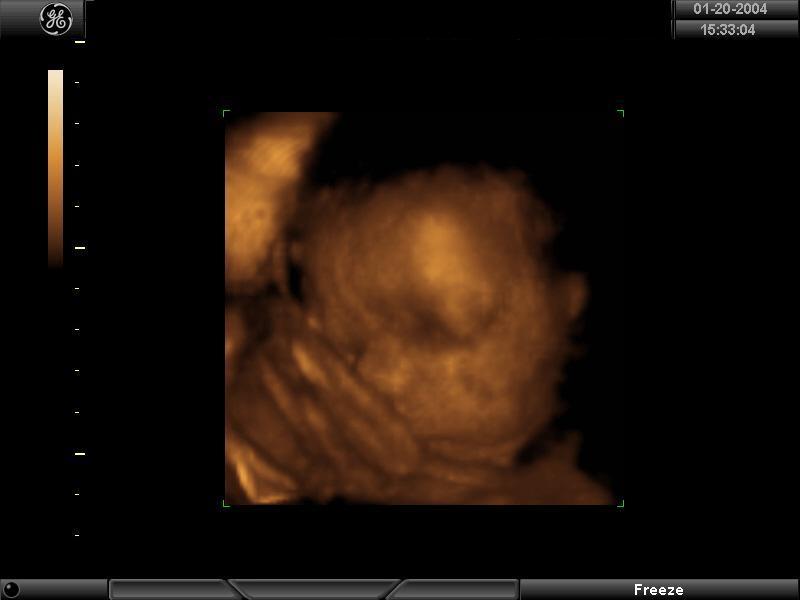

1/20/04

One of the things I've really looked forward to was the 4-D ultrasound. It's 4-D because not only does it show the baby in 3-D, but there is movement, too. Today was my 29 week appointment and (at last!) the day of the super-tech portraits!!

The sonographer had a hard time getting him to move his face directly toward us. The entire time, either his cord was in the way or his hand (and sometimes his foot) was in his face. So the pictures are mostly profiles, but I was still excited to see that. The doctor, though, thought I might be able to get a good front facial view at my next appointment, so he rescheduled me in two weeks for a re-do at no charge! I can't complain about that!!

Before the ultrasound, I ate some cookies and drank some apple juice hoping to see the baby in action, but as it turned out, it was better for him just to be still so he could have his picture made for the first time. Like last time, we got a VHS of the regular sonogram, plus this time included a CD-R of the still portraits and some black and white print-outs. I've included two of my favorite shots below, in both black and white and in the "gold tone." She said these pictures don't show hair, but I don't know. . .